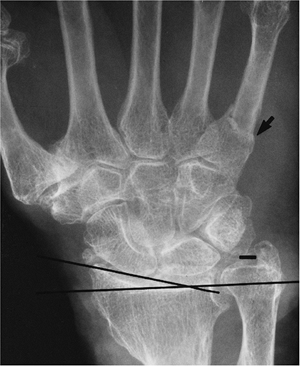

![]() |

FIGURE 9-4 PA radiograph of an old Colles fracture with shortening of the radius and decreased radial inclination (lines). There is degenerative arthritis and an associated fifth metacarpal fracture (arrow).

|